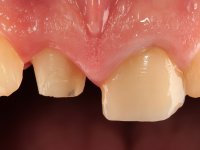

Male patient, 45 years old, smoker, with oesophageal reflux and poor oral hygiene. Teeth 11 and 21 presented an endodontic treatment and tooth 21 was rehabilitated with a Richmond type crown done 12 years ago. Tooth 11 presented an extensive restoration in composite resin in the buccal surface bonded exclusively to dentin. The palatal surface presented acid erosion and an extensive reconstruction in the endodontic access. The clinical crown was 4,5mm height and the root had 11mm.

After a previous dental impression in silicone to construct a provisional crown with the original shape, a tooth preparation was done following the principles of the Richmond crown. The intra-coronal preparation was done only until the enamel-cement line, without including the root.